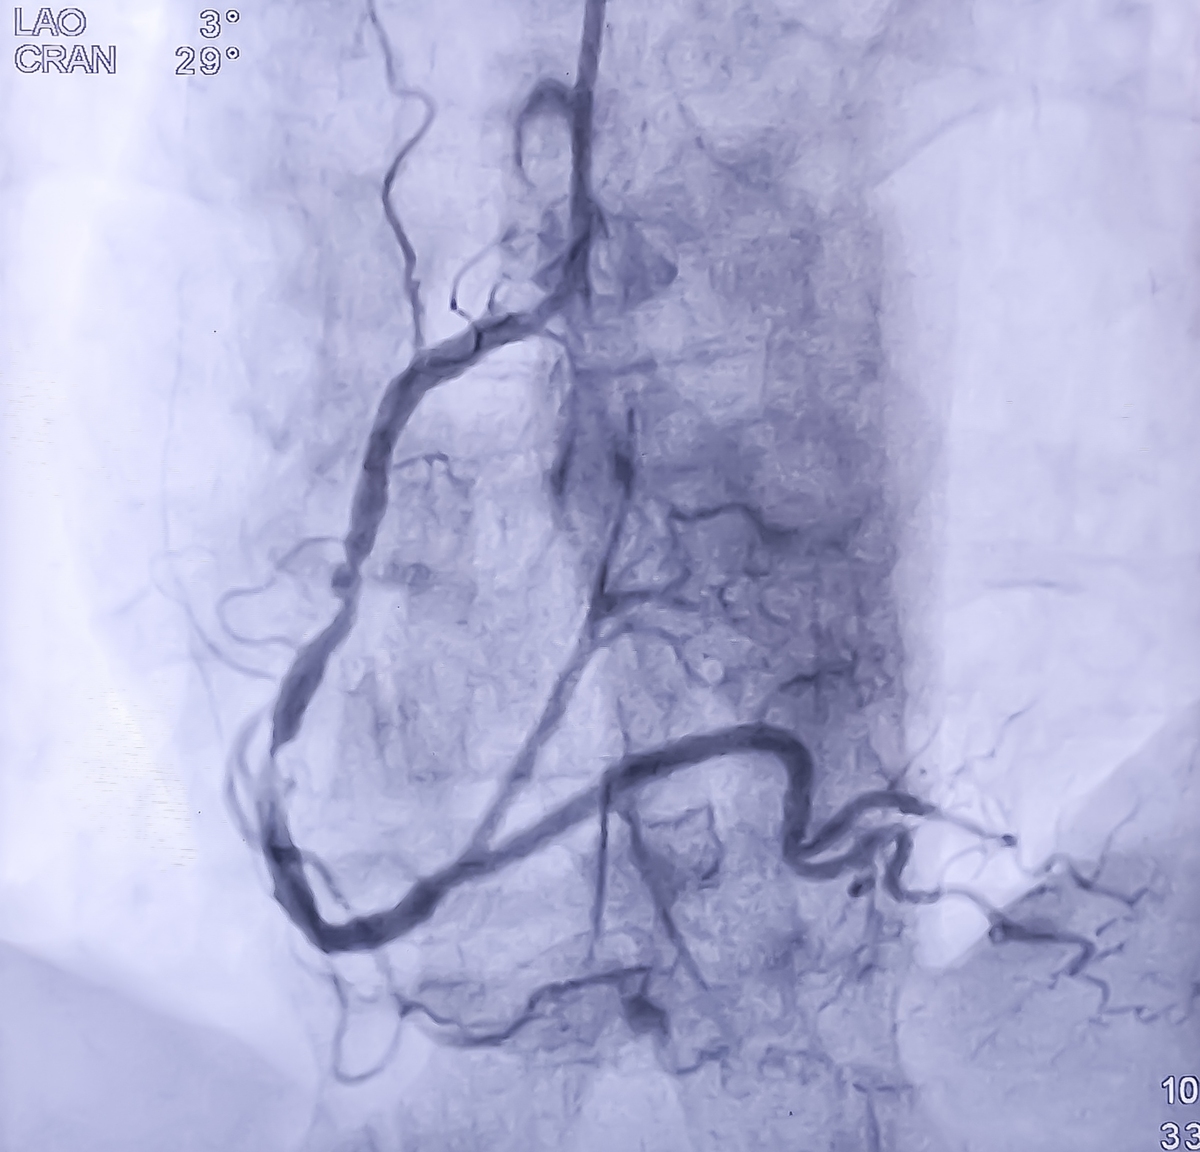

纠错:对比增强超声被用于诊断右颈动脉的破裂易损斑块,该斑块伴有溃疡形成、游离血栓以及右颈内动脉起始处的轻度狭窄。DSA 和 CTA 进一步证实了该诊断。患者还出现了右侧尾状核的急性腔隙性梗死,这表明脑血管事件与斑块破裂和血栓形成之间存在关联。神经科医生实施了支架置入术和球囊血管成形术,在患者颈动脉游离血栓的远端使用保护伞。手术后,未观察到新的神经症状,患者病情好转后出院。